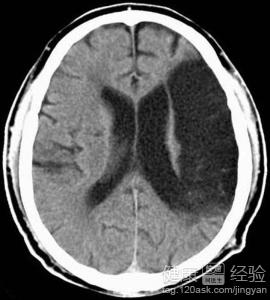

上個月的時候,爺爺在家裡突然的呼吸不順暢,而且心跳的特別的快。當時是中午,我爸媽都在家裡午睡,奶奶也在午睡,只我和爺爺不困我兩在下象棋。當時我一看爺爺不對就馬上叫醒我爸媽帶爺爺去醫院,到醫院經過檢查後,醫生說爺爺腦出血,幸好來的及時。現在與大家一起分享!

1內科治療:患者出血量不多,神經損害不重的情況下可以不選擇手術治療。一向可以讓患者多休息,然後控制患者的血壓,一般可以使用普通藥物進行控制血壓就可以。如果患者有嘔吐的現在可以使用止吐劑。

2手術治療:手術治療也要看患者出血的地方在哪,而且要了解出血的情況,檢查清楚後要確定一個完善的方案後再進行手術。手術可以開顱清除血腫,也可以穿刺進行抽吸血腫治療。